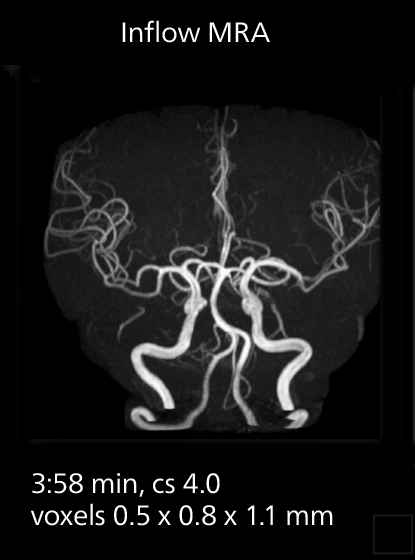

Crisp images are obtained with high resolution and short scan times using Elition X. A cyst can be seen.